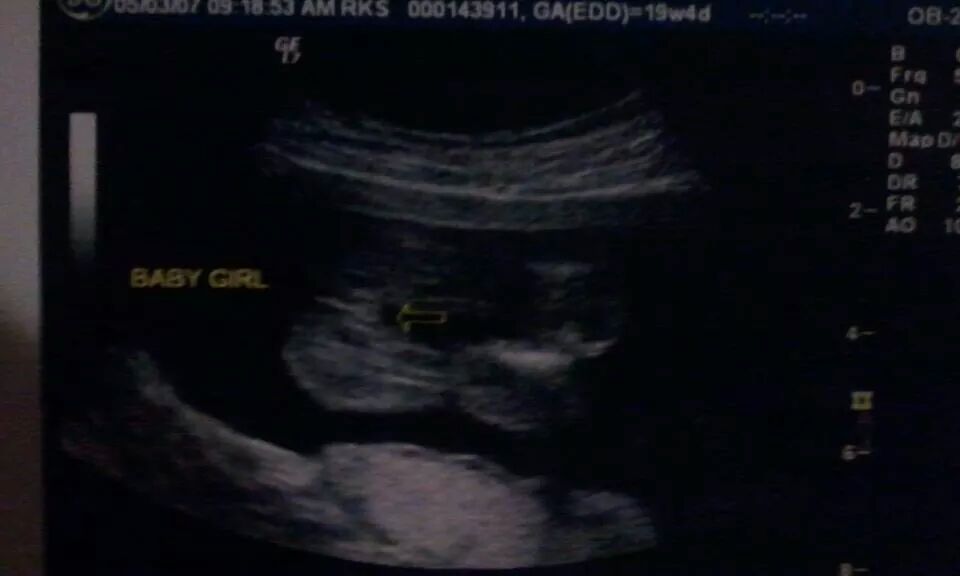

I am curious to see what you guys think I am having, I'm 21 weeks in this picture. So please let me hear your opinions!Attachment 21633

HMMMMM. MAYBE GIRL? IMAGE IS NOT VERY CLEAR AT ALL...SO I WOULDN'T BET MY MONEY ON IT.

See , I thought it's not that clear as well..... They told me girl but I have some doubts.

Thank you for the input, I'm not convinced it is a girl yet. I want to be 100% sure that it is in fact a babygirl before I start buying pink stuff! lol